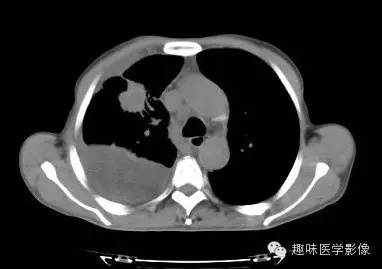

CT: 右侧胸廓缩小。右肺上叶前段结节,略分叶,可见长短不一毛刺,胸膜牵拉征及血管集束征,右肺组织向肺门萎陷,左肺清晰,未见异常。纵隔内见淋巴结肿大(4R淋巴结增大)。右侧前壁及侧后胸壁包裹性积液征象。

右上肺周围型肺癌,纵隔淋巴结转移,胸膜腔包裹性积液。